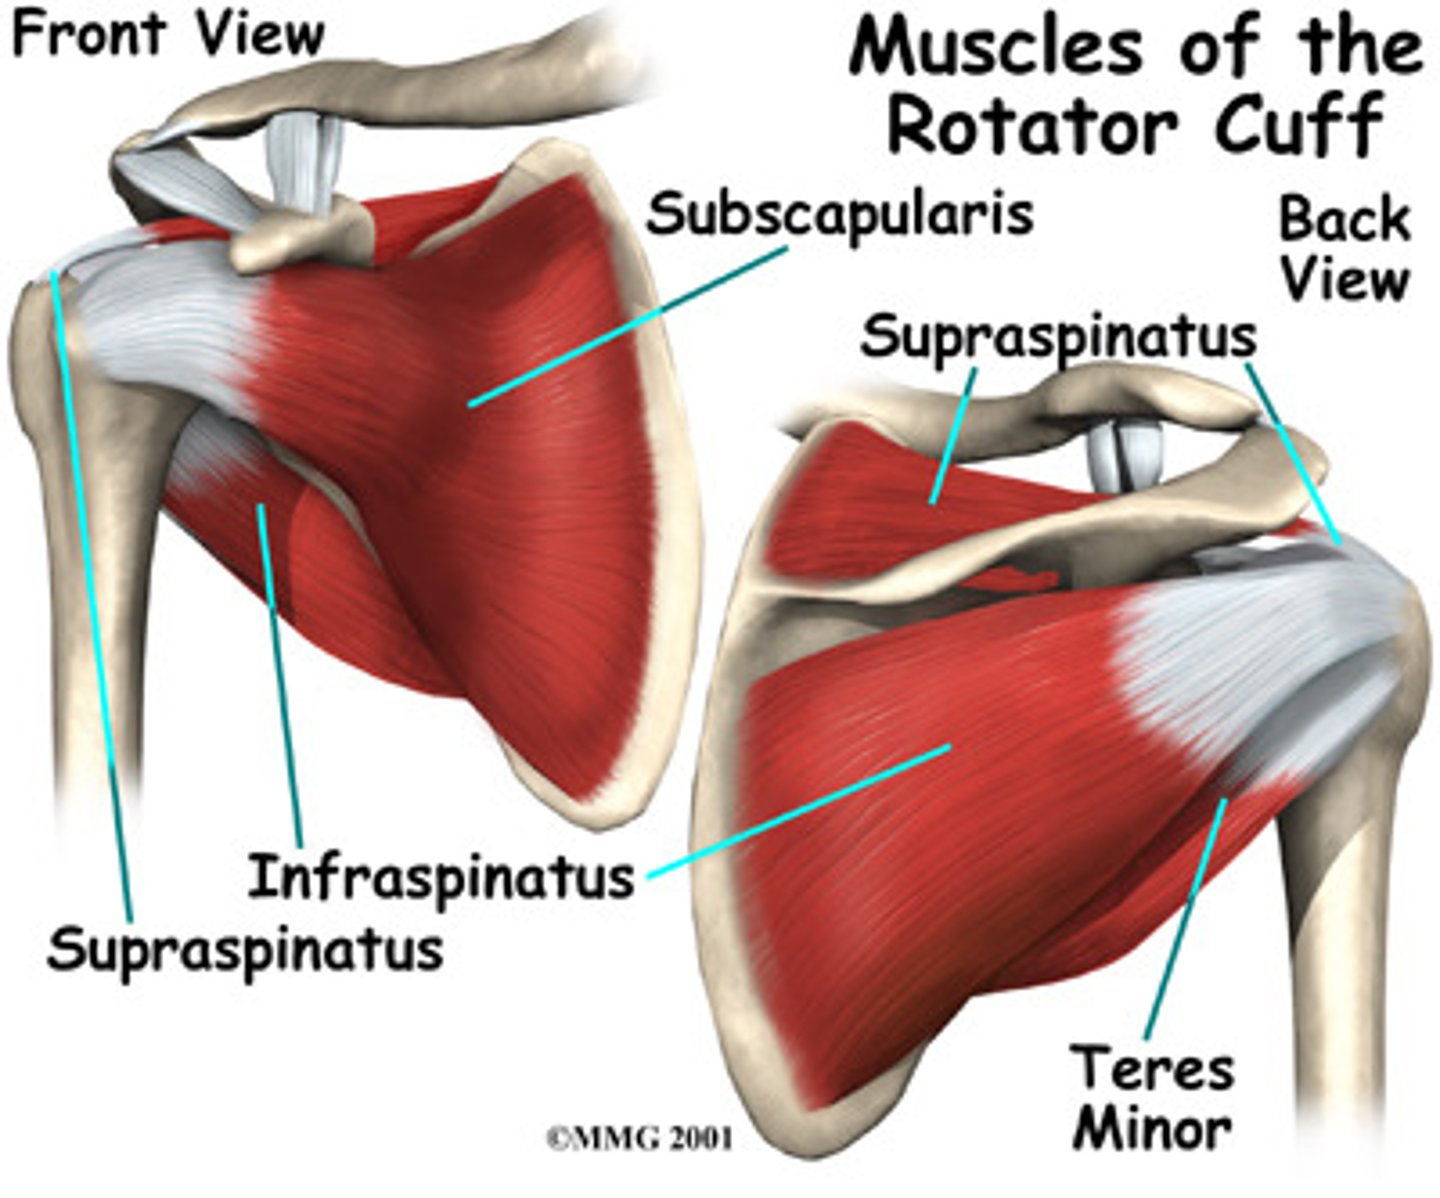

(Scapulohumeral muscles (intrinsic shoulder):) Rotator cuff muscles

Supraspinatus, Infraspinatus, Teres Major, Subscalpularis

(Rotator Cuff Muscles:) Supraspinatus

-Abduction of arm (assists deltoid in the initial 15˚)

-Suprascapular n. (C5 - C6)

(Rotator Cuff Muscles:) Infraspinatus

-Laterally rotates arm

-Suprascapular n. (C5 - C6)

(Rotator Cuff Muscles:) Teres Major

-Laterally rotates arm

-Axillary n. (C5 - C6)

(Rotator Cuff Muscles:) Subscapularis

-Medially rotates arm

-Upper and lower subscapular nerves (C5 - C7)